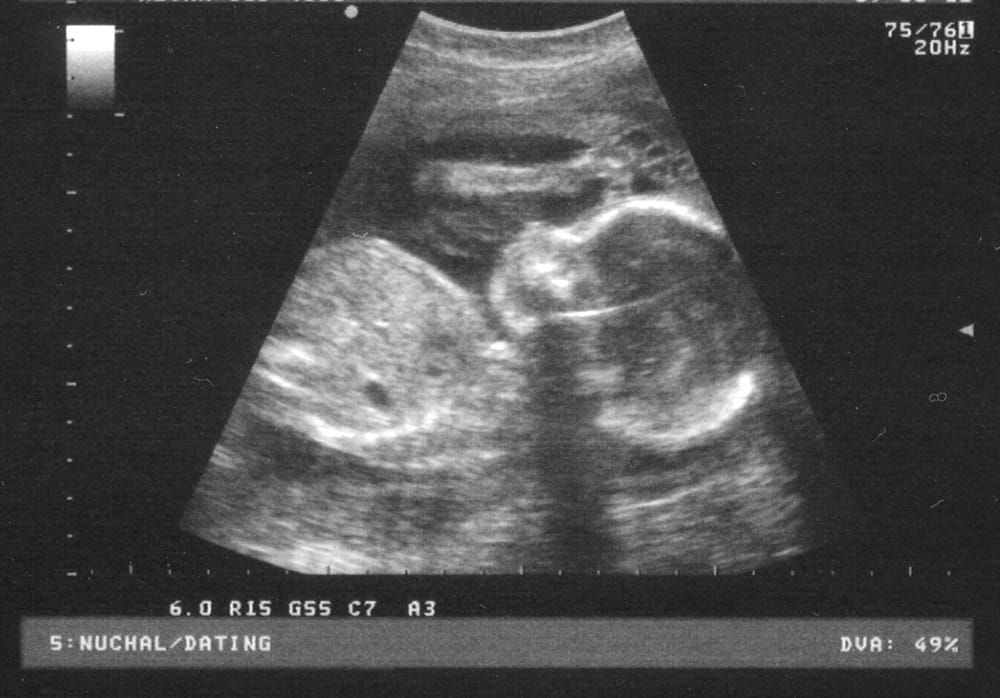

However different American healthcare is from British healthcare, it wouldn’t be unreasonable to assume that the principles of consent are similar. One such principle is that valid consent needs to be informed; one must be aware of the implications of a decision to have a procedure, the benefits, risks and so on. When it comes to abortion, it seems people cannot agree on what it means to be informed. Some Americans feel that to be sufficiently informed about a decision to terminate one’s pregnancy a woman must undergo transvaginal ultrasound. They refer to this together with the provision of other information as “the right to know”.

Why would a transvaginal ultrasound be performed in the context of abortion? In Britain, it wouldn’t. Over here, transvaginal ultrasound is used to examine the womb, ovaries and other organs for any abnormalities: it is a diagnostic tool. Other than letting a woman know she has a baby, which one suspects she already knows, the purpose of the transvaginal ultrasound in a healthy pregnancy was initially unfathomable to me.

Although it could have helped illustrate the issues, I will refrain from comparing abortion to any other operation as such a decision is vastly more complex. A better way to look at the compulsory inclusion of transvaginal ultrasound may be to disregard the controversies surrounding abortion itself and focus on what it means to be informed about a decision. The objective of providing information to make a decision is neither to condemn nor promote a choice. In fact, it is unethical to impose an option on a person; that person has the right to make autonomous decisions regardless of how unwise that decision appears to others. Absurdly it has been said that the idea is to put a woman off having an abortion by forcing her to look at the image of her foetus. Maybe they haven’t checked but even if one could justify why a woman should be persuaded not to have an abortion, this experience is highly unlikely to change her mind!

Before anyone goes as far as to say that denying a woman a transvaginal ultrasound is depriving her of vital information that she needs to give informed consent, perhaps they should ask themselves two questions. Firstly does it override a person’s autonomy to include dissuasion in the process of informing consent? And secondly is it acceptable for an invasive procedure such as transvaginal ultrasound, which is of no visible benefit to any party, to be a hoop through which a pregnant woman must jump before she can have an abortion?